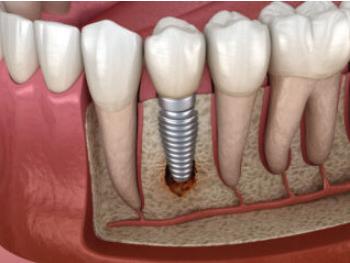

Peri-Implantitis Understanding and Preventing Implant Complications

Dental implants have revolutionized modern dentistry, providing an effective solution for replacing missing teeth. However, as with any medical procedure, complications can arise. One such complication is periimplantitis, an inflammatory condition that affects the soft and hard tissues surrounding dental implants. In this article, we will delve into the causes, symptoms, treatment, and prevention of peri-implantitis.

Understanding Peri-Implantitis

Peri-implantitis refers to the

inflammation and subsequent destruction of the tissues surrounding dental implants. It is primarily caused by bacterial infection and is characterized by pus, bleeding, swelling, and the loss of supporting bone. Poor oral hygiene, smoking, systemic diseases, genetic factors, and implant-related factors such as surface roughness or misfit can contribute to the development of peri-implantitis.

Recognizing the Symptoms

Early detection of peri-implantitis is crucial for successful treatment. Some common symptoms include bleeding upon probing, swelling or redness around the implant site, pain or discomfort, and increased pocket depth around the implant. Patients with dental implants should be vigilant in monitoring these signs and seek professional assistance if any concerns arise.

Treatment Options

The treatment of peri-implantitis depends on the severity of the condition. In its initial stages, non-surgical approaches such as professional clean-

ing, meticulous oral hygiene instructions, and antimicrobial therapy may be sufficient. However, advanced cases may require surgical intervention, including implant surface decontamination, bone grafting, or guided tissue regeneration. It is essential to consult with a dental professional who specializes in implantology for appropriate diagnosis and treatment planning.

Prevention is Key

Prevention plays a crucial role in minimizing the risk of peri-implantitis. Maintaining excellent oral hygiene practices, including regular brushing, flossing, and interdental cleaning, is paramount. Routine dental visits for professional cleanings and check-ups allow early detection of any implantrelated issues. Additionally, avoiding tobacco use and managing systemic conditions, such as diabetes, can significantly reduce the risk of complications.

Peri-implantitis is a concerning

complication that can compromise the success of dental implants. Recognizing the symptoms and seeking timely treatment are vital for a positive outcome. Furthermore, adopting preventive measures, including diligent oral hygiene practices and regular dental visits, can greatly reduce the risk of developing peri-implantitis. By staying informed and proactive, individuals with dental implants can maximize their oral health and enjoy the long-term benefits of their restorative treatment. Remember, a healthy implant requires a healthy foundation.